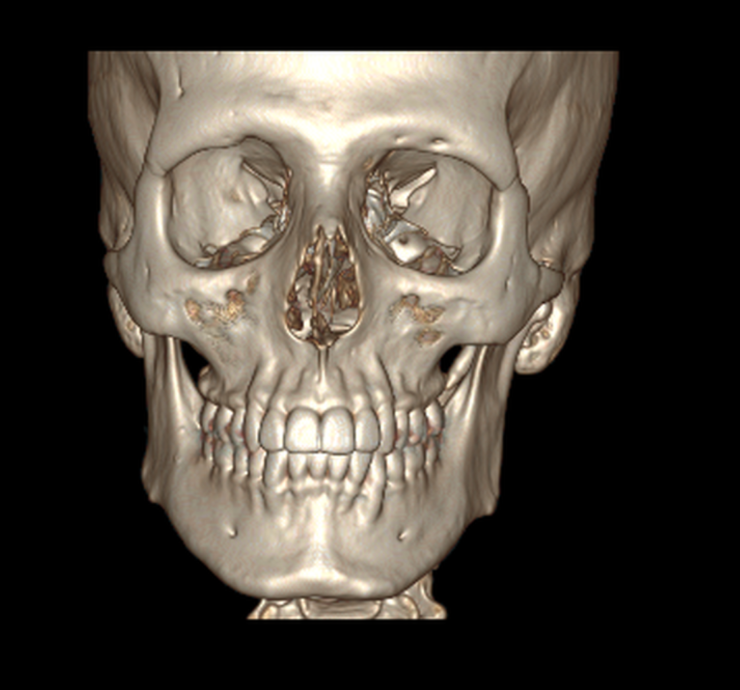

after talking to chatgpt here is what it recommends:

1. sliding genio

2. custom PEEK infraorbital implants

3. slight buccal fat removal

after talking to chatgpt here is what it recommends:

1. sliding genio

2. custom PEEK infraorbital implants

3. slight buccal fat removal